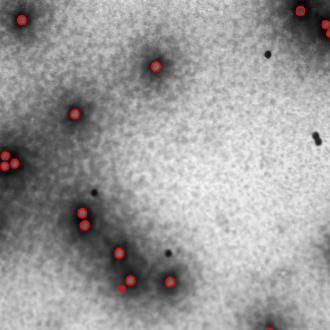

Regular monitoring of the primary particles and purity profiles of a drug product during development and manufacturing processes is essential for manufacturers to avoid product variability and contamination. Transmission electron microscopy (TEM) imaging helps manufacturers predict how changes affect particle characteristics and purity for virus-based gene therapy vector products and intermediates. Since intact particles can characterize efficacious products, it is beneficial to automate the detection of intact adenovirus against a non-intact-viral background mixed with debris, broken, and artefact particles. In the presence of such particles, detecting intact adenoviruses becomes more challenging. To overcome the challenge, due to such a presence, we developed a software tool for semi-automatic annotation and segmentation of adenoviruses and a software tool for automatic segmentation and detection of intact adenoviruses in TEM imaging systems. The developed semi-automatic tool exploited conventional image analysis techniques while the automatic tool was built based on convolutional neural networks and image analysis techniques. Our quantitative and qualitative evaluations showed outstanding true positive detection rates compared to false positive and negative rates where adenoviruses were nicely detected without mistaking them for real debris, broken adenoviruses, and/or staining artefacts.